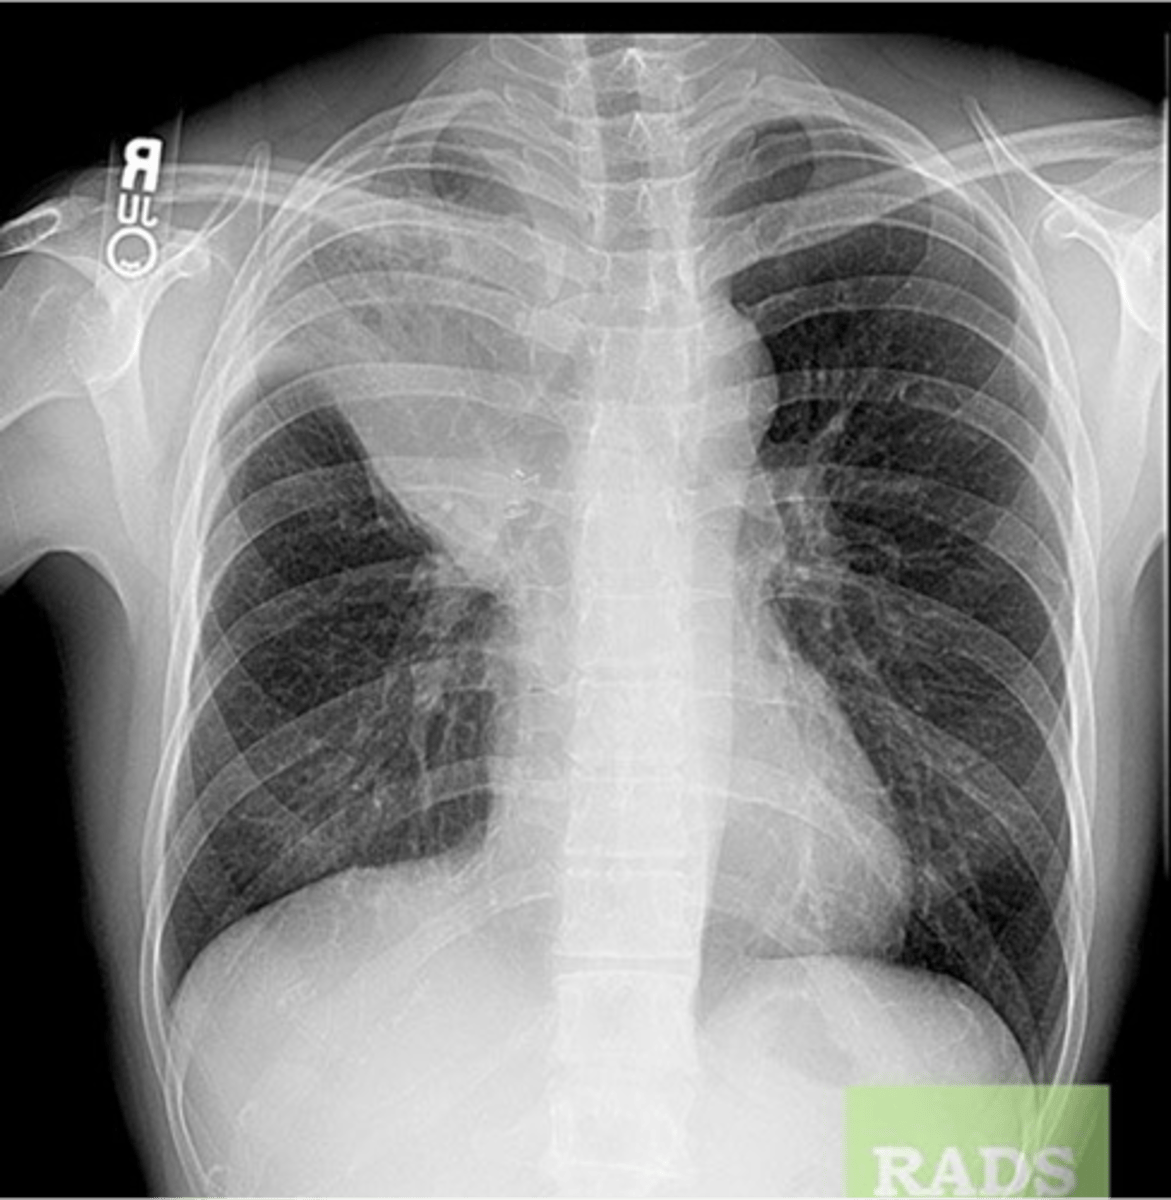

Tension pneumothorax

knowt flashcard image

Tension pneumothorax (right)